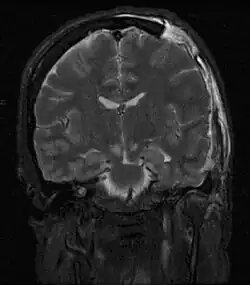

Rezonans magnetyczny

Rezonans magnetyczny (MRI) ze względu na długi czas badania, mniejszą dostępność i wyższy koszt w porównaniu do tomografii komputerowej ma dość ograniczone zastosowanie w diagnostyce i ocenie zaawansowania nowotworu jądra[169]. Rezonans magnetyczny osiąga podobną skuteczność w ocenie zajęcia węzłów zaotrzewnowych jak tomografia komputerowa[175][176][177], jednak może być przydatny gdy inne metody diagnostyczne dają niejednoznaczne wyniki lub w przypadku nadwrażliwości na jodowe środki kontrastowe[177]. Metoda nie jest szeroko stosowana w diagnostyce guza pierwotnego, choć bywa wykorzystywana w przypadku niejednoznacznych wyników badania ultrasonograficznego[169].